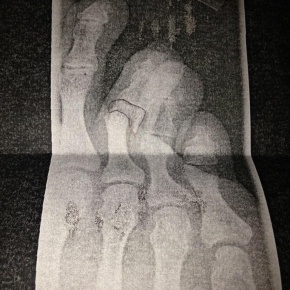

La rotura de dos huesos de un pie del frontman Matthew Bellamy han provocado que Muse cancelen sus próximos conciertos en Oslo (Noruega), Estocolmo (Suecia) y Malmo (Suecia). Los siguientes conciertos si bien no han sido cancelados se llevarán a cabo si Bellamy mejora.

Matt Bellamy se rompe dos huesos del pie